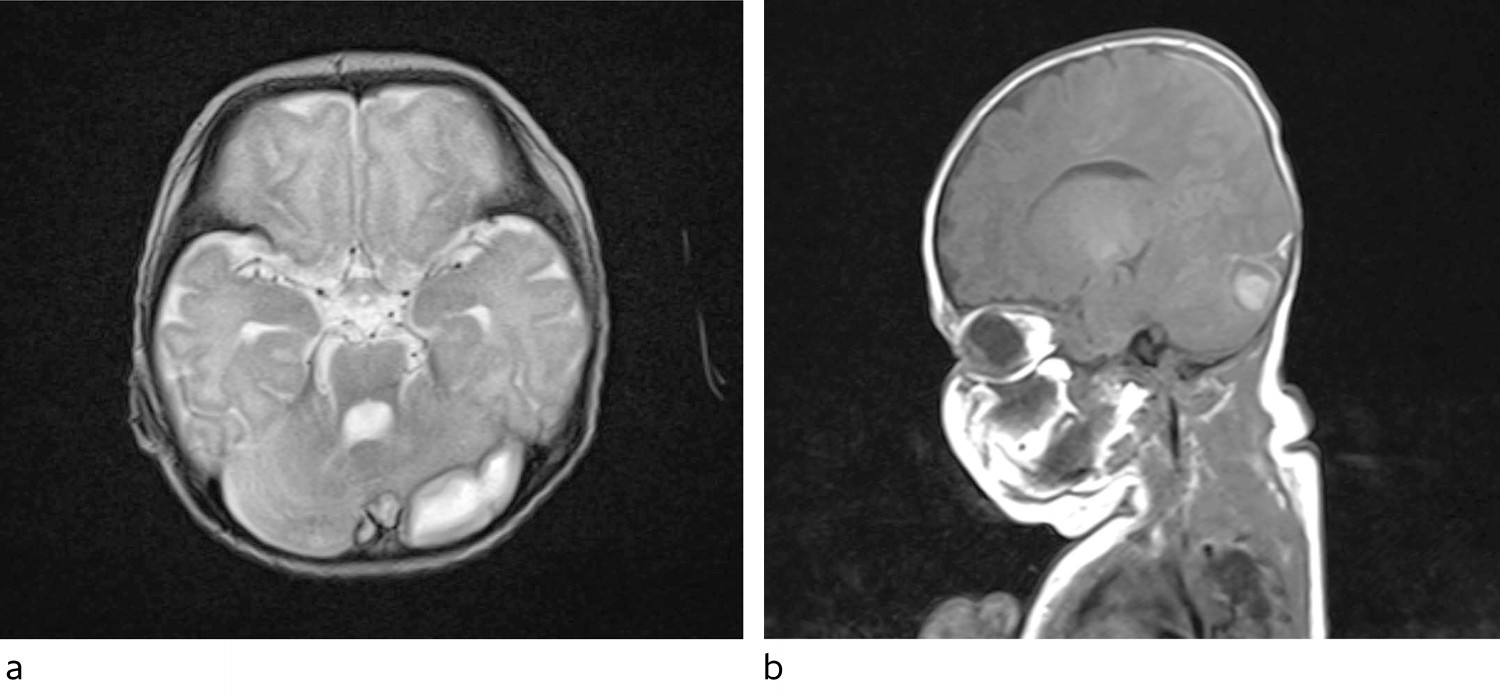

Klinisk var tilstanden stabil de påfølgende dagene. Det ble tatt daglige blodprøver, og CRP steg igjen til 180 for så å holde seg stabil i underkant av 200. Kroppstemperaturen var fortsatt svingende, og pasienten hadde gode perioder, men var også trøtt og sov mye. Det hadde blitt tatt ultralyd caput tre ganger i forløpet. De to første undersøkelsene viste tegn på ventrikulitt, den tredje var i det vesentlige normal. På bakgrunn av vedvarende høy CRP og fortsatt feber en uke ut i forløpet ble det besluttet at det var indikasjon for MR caput/columna med spørsmål om abscesser. MR-undersøkelsen viste omfattende trombosering av vener og venesinus samt flere abscesser (figur 1), hvorav den største ble målt til 3 × 1,2 × 1,3 cm. Det ble startet med enoksaparin som trombosebehandling (4,5 mg × 2 subkutant, gradvis justert opp til 7,5 mg × 2 monitorert etter anti-faktor Xa-verdi).

Ultralyd caput er den foretrukne billedundersøkelsen hos nyfødte med meningitt, og anbefales for alle hvor dette mistenkes. Undersøkelsen har høy sensitivitet for å avdekke ventrikulitt, hjerneødem og økt intracerebral væske. Imidlertid er MR overlegent når det gjelder forandringer i hjernevev, som f.eks. ved abscessdannelse. Dette gjelder særlig forandringer i bakre skallegrop (10). Hos vår pasient var det subtile tegn til ventrikulitt på ultralyd caput, men dette var i bedring tredje gang undersøkelsen ble utført. Ventrikulitt kan forhindre drenasje av cerebrospinalvæske og fører ofte til at den inneholder bakterier lenger enn ved meningitt uten ventrikulitt. I noen tilfeller kan ekstern drenasje og direkte instillasjon av antibiotika i ventriklene bli aktuelt. Det ble ikke vurdert i vårt tilfelle. Det var ikke mulig å se abscessutviklingen på ultralydundersøkelsene, verken den store abscessen beliggende over venstre cerebellarhemisfære eller de mindre abscessene langs venstre temporallapp. Det var heller ingen mistanke om venetrombose på ultralyd.